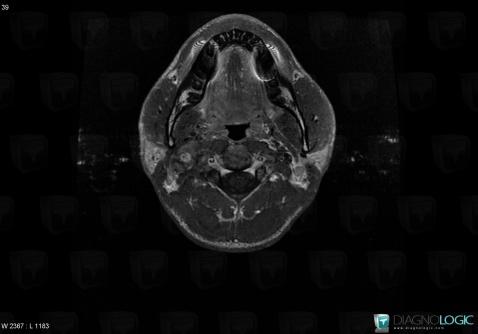

Schwannome, Espaces profonds de-face, IRM

Voici les informations spécifiques à l'image clé ci dessus:

- Diagnostic Schwannome, Localisation(s) Espaces profonds de la face, comportant les gammes Masse solide cervicale, Lésion de l'espace carotidien